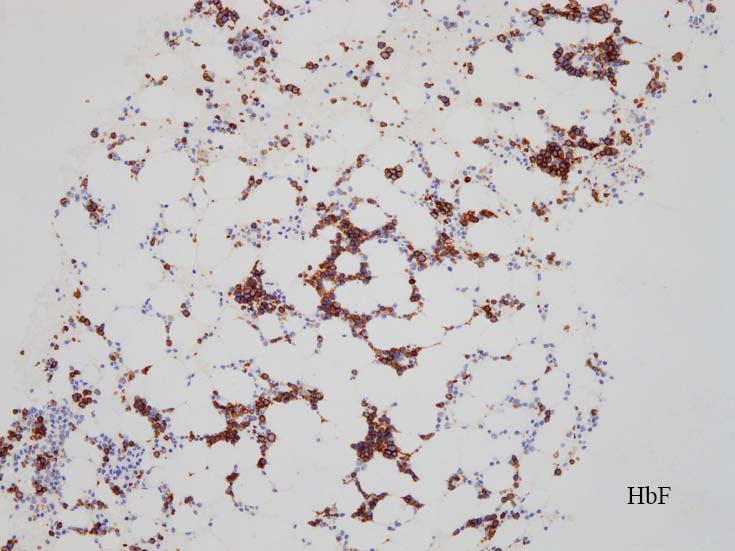

骨髄赤芽球のHbF発現

Choi JW, et al. Significance of fetal hemoglobin-containing erythroblasts (F blasts) and the F blast/F cell ratio in myelodysplastic syndromes.

Leukemia. 2002 Aug;16(8):1478-83.PMID:12145688

Iwasaki T, et al. Characterization of myelodysplastic syndrome and aplastic anemia by immunostaining of p53 and hemoglobin F and karyotype analysis: differential diagnosis between refractory anemia and aplastic anemia.Pathol Int. 2008 Jun;58(6):353-60.PMID:18477214

MDS症例のHbF発現.

サムネイル画像をクリックすると大きな画像が見られます.

MDSでの赤芽球HbF発現は, 陽性細胞はそれほど多くない印象ですが, この低形成性MDS症例では, 多くの陽性細胞がaggregatesを形成していました.